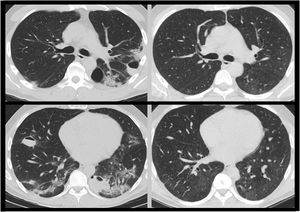

After discharge, self-limited haemoptoic expectoration was presented. A thoracic computed tomography scan showed multiple bilateral cavitated pulmonary lesions, and was readmitted to hospital. Physical examination and primary blood analysis were normal. A bronchoscopy was performed showing hematic secretions in the left lower lobe. All microbiological samples were negative.

In absence of clinical manifestations and given the normality of the studies, the case was classified as post-COVID bullous disease, and an ambulatory thoracic CT scan was performed after 3 months, showing radiological resolution of lesions (Fig. 1) and normal respiratory function test.